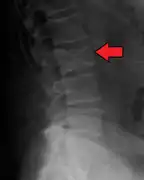

The diagnostic examination of a person with suspected multiple myeloma typically includes a skeletal survey. This is a series of X-rays of the skull, axial skeleton, and proximal long bones. Myeloma activity sometimes appears as "lytic lesions" (with local disappearance of normal bone due to resorption). And on the skull X-ray as "punched-out lesions" (raindrop skull). Lesions may also be sclerotic, which is seen as radiodense.[59] Overall, the radiodensity of myeloma is between −30 and 120 Hounsfield units (HU).[60] Magnetic resonance imaging is more sensitive than simple X-rays in the detection of lytic lesions, and may supersede a skeletal survey, especially when vertebral disease is suspected. Occasionally, a CT scan is performed to measure the size of soft-tissue plasmacytomas. Bone scans are typically not of any additional value in the workup of people with myeloma (no new bone formation; lytic lesions not well visualized on bone scan).

Pathological fracture of the lumbar spine due to multiple myeloma